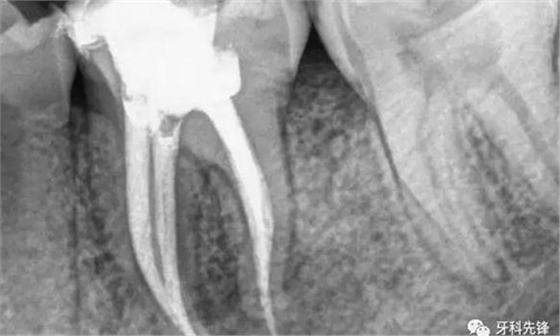

根管治療后需要做牙冠,原因有三

1、因為需要進行根管治療的牙齒,一般已經是蛀牙缺損很大,這個時候雖然根管治療完成,但是剩下的牙體組織非常脆弱,容易折斷、裂開,失去正常的功能,單純用材料已經沒法恢復功能。

2、根管治療是以藥物,以及器械的操作來將根管內的殘渣,以及細菌盡可能地清除消毒干凈。然而,這樣的消毒過程如果要認真的進行,卻必須去除掉不少被細菌感染的牙齒,以及不得不修正的牙體組織。所以大部分的牙齒一旦進行根管治療,則可能不太足夠支持咀嚼的力量而可能斷裂,單純用材料已經沒有辦法恢復功能,即使能恢復長遠效果也不好。

3、經過根管治療后的牙齒失去了來自牙髓的營養(yǎng)供應,就像失去樹根的樹木一樣,慢慢枯萎變的很脆弱,造成牙齒的脆性增加,易劈裂。

由于這3個方面的原因,整個牙齒的支持力量明顯減弱,可能在某些特定條件下不足以支持咀嚼壓力而容易發(fā)生牙冠劈裂,所以要及時做個牙冠把牙齒保護起來。

當牙齒做完根管治療,由于牙齒自身的結構及治療的需要,牙冠中心一般都是空的,這時,如果直接做牙套,其抗折斷力很差,一般都需要在牙根上打上樁釘,做出個結實的核,以對抗牙齒使用中的折斷力。